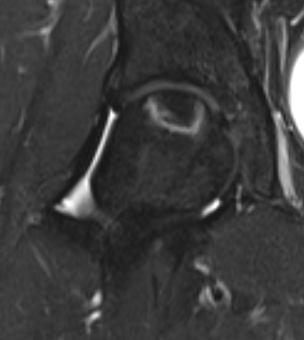

Modified Kerboul Combined Necrotic Angle (CNA)

Adding the arc of the femoral head necrosis

- mid-sagittal and mid-coronal MRI

- low risk collapse: < 190 degrees

- moderate risk collapse: 190 - 240 degrees

- high risk collapse: > 240 degrees

Natural history

Kerboul CNA

- CNA > 240: 100% collapse

- CNA 190 - 240: 50% collapse

- CNA < 190: 0% collapse